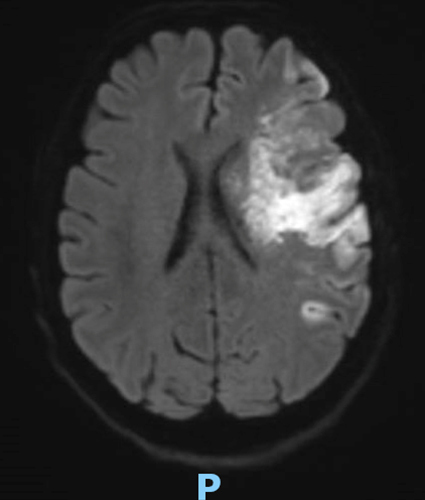

Le type d’hémianopsie est très important car il permet de localiser une atteinte neurologique, en connaissant le trajet des voies optiques.

Figure d’après le Collège des enseignants de neurologie (CEN). Altération aiguë de la vision.

Cette question supposait d’avoir bien en tête le schéma des voies optiques, et d’avoir des repères sur les principaux territoires vasculaires cérébraux et l’atteinte clinique associée. Il bien mentionné par le CEN que l’hémianopsie latérale homonyme gauche peut se voir dans un AVC sylvien superficiel droit.

Tableau d’après le Collège des enseignants de neurologie. Altération aiguë de la vision.